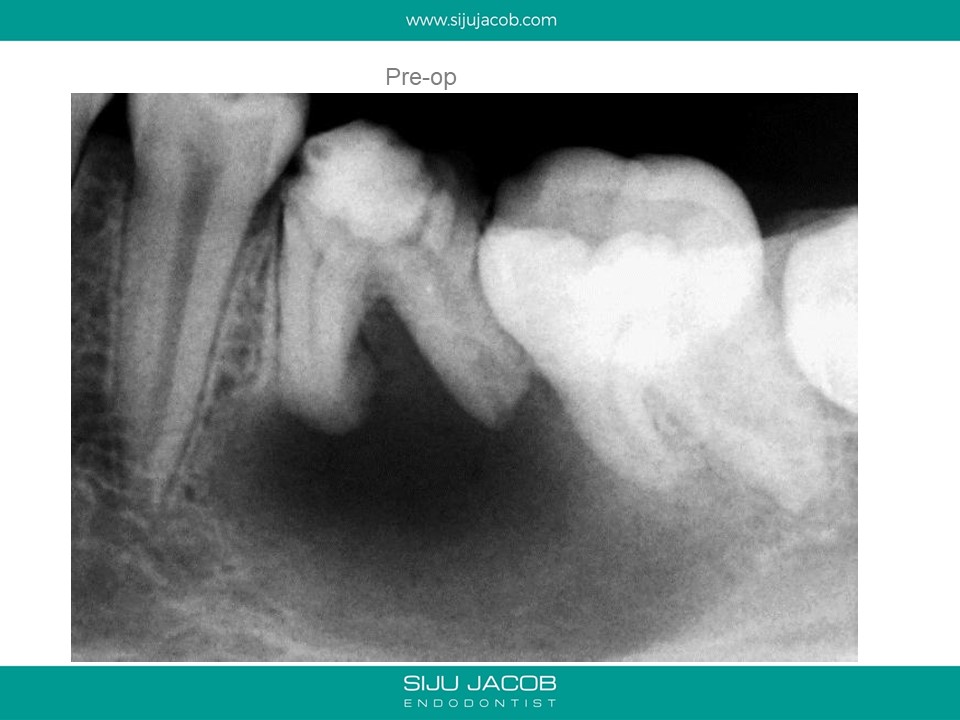

This was a 15 year old girl with a large peri-apical lesion in relation to the the left mandibular first molar. The tooth had a guarded restorative prognosis. The goal of endo in this case was to hold the tooth for a longer period before placing implants and also get some bone to fill in which would make implant placement more viable. I held the tooth with calcium hydroxide dressing for 5 months, saw some bone-fill and obturated the tooth. A crown was also placed. 3-year recall shows the tooth still going strong.